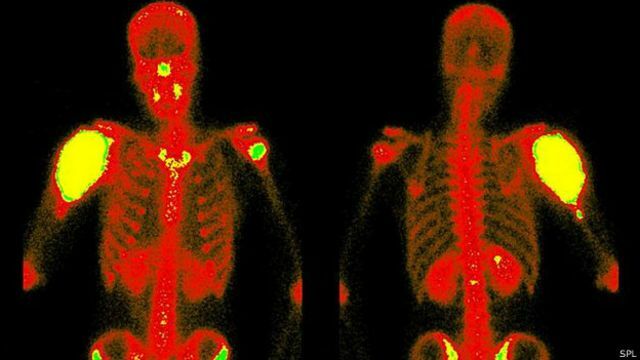

Elemento que puede hacer brillar los huesos fue descubierto por Pirrie y Segre, fisios italianos, utilizados en medicina nuclear para pruebas diagnosticas.

Kuhl y Edwards presentan la tomografía computarizada por emisión de fotón único.